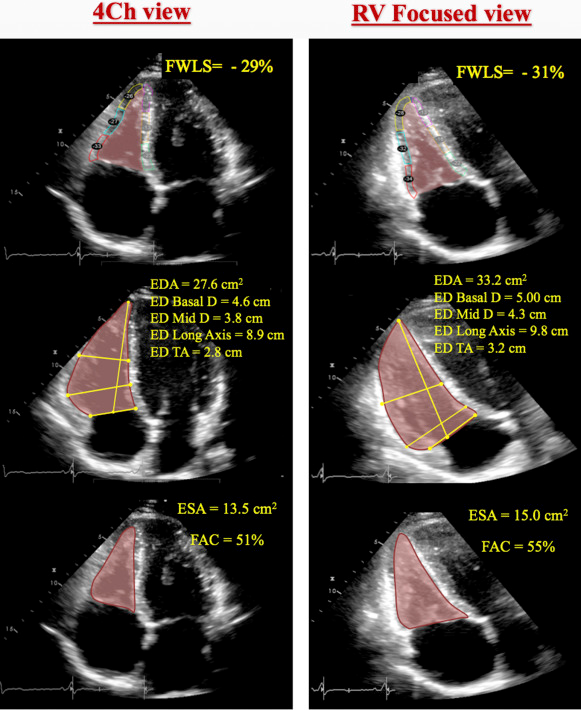

The conventional apical four-chamber view (i.e., focused on the left ventricle) results in considerable variability in how the right heart is sectioned, and consequently, RV linear dimensions and areas may vary widely in the same patient with relatively minor rotations in transducer position (Figure 7B). RV dimensions are best estimated from a RV-focused apical four-chamber view obtained with either lateral or medial transducer orientation (Figure 7A and Table 7). Care should be taken to obtain the image with the LV apex at the center of the scanning sector, while displaying the largest basal RV diameter and thus avoiding foreshortening. Of note, the accuracy of RV measurements may be limited when the RV free wall is not well defined because of the dimension of the ventricle itself or its position behind the sternum. Recent data have suggested that indexing RV “size” to BSA may be relevant in some circumstances, but the measurements used in those studies lacked the reference points of the RV-focused view and frequently used RV areas, rather than linear dimensions. 2

- 🌟RV focused A4C View: LV apex is at the top of the view, but angulated transducer to tip the RV into better view. This view allows you to measure the maximal RV diameter.

- This is the view that you will want to use to take measurements for RV size

See the following image from 3 that helps illustrate the importance of getting the optimal view for RV size assessment:

Fractional Area Change (Poor Man’s EF)

- Obtain in RV focused A4C view

- Values < 35% are consistent with RV dysfunction

RV Systolic Strain

Longitudinal strain is calculated as the percentage of systolic shortening of the RV free wall from base to apex, while longitudinal strain rate is the rate of this shortening. 2

- Abnormal if values are less negative than -25% (or lower than 25% in absolute value)

- Should be measured in the RV-focused A4C view